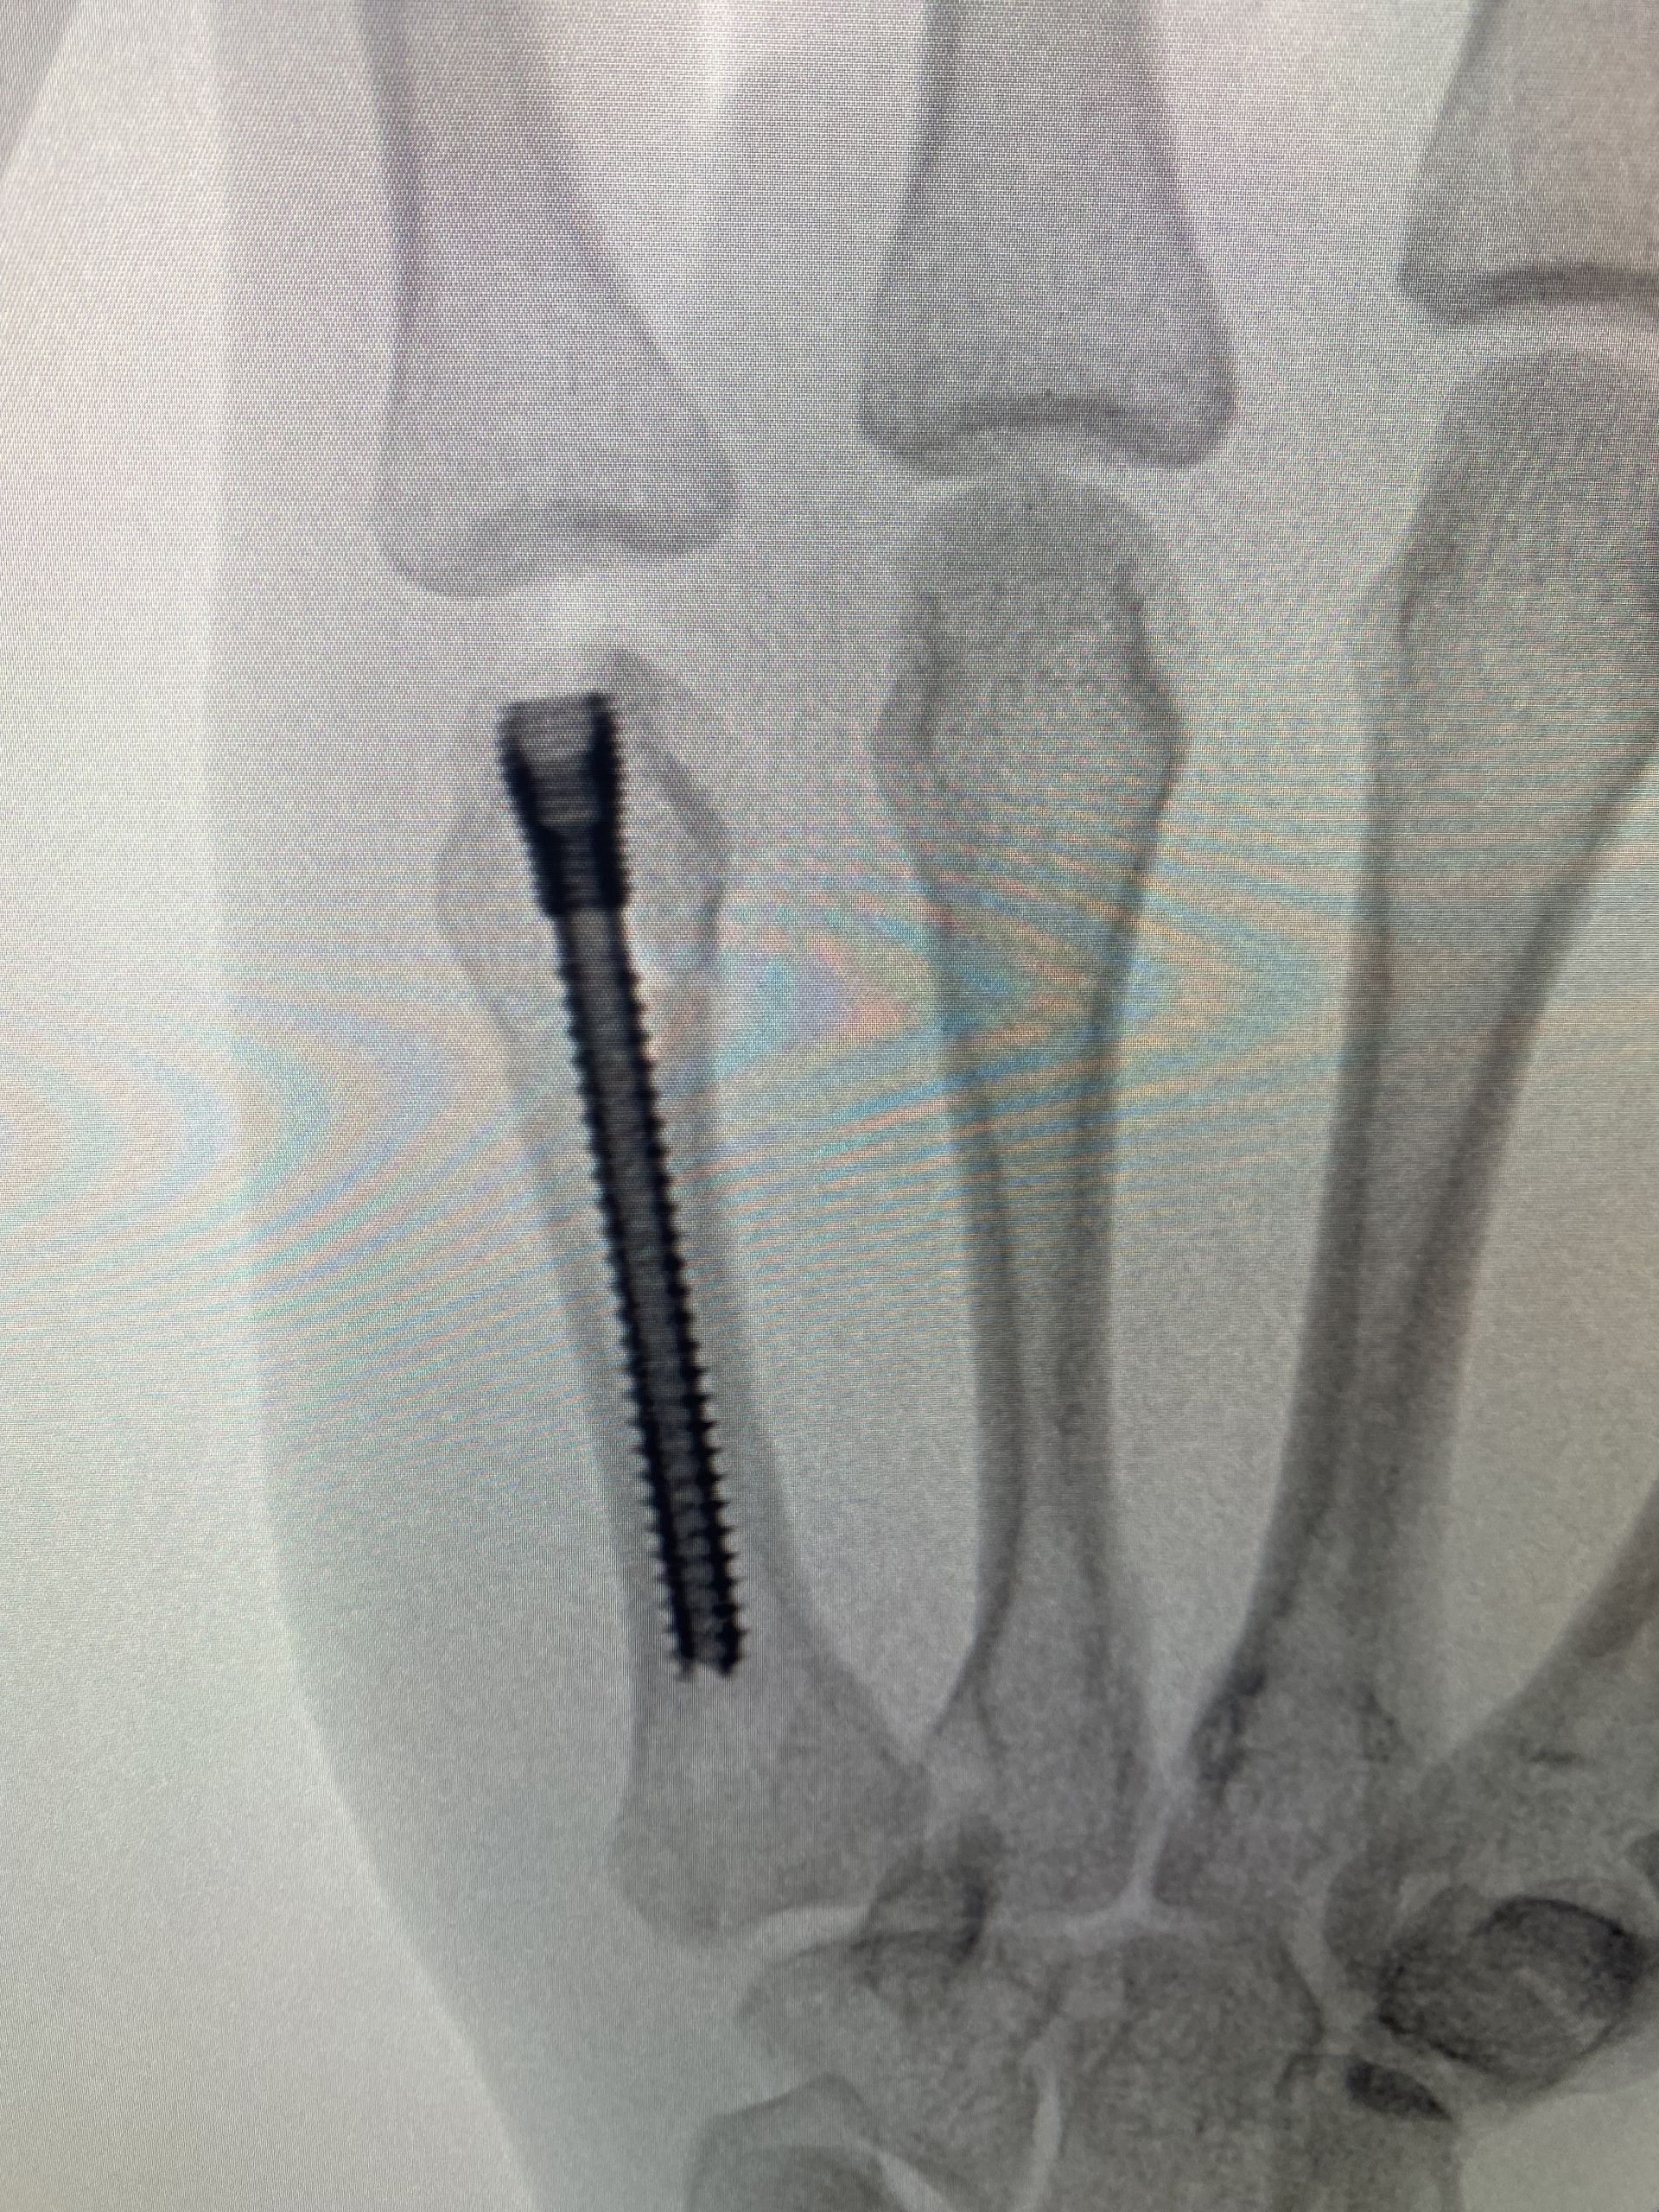

A técnica de parafuso intramedular é menos invasiva e foi descrita pela primeira vez em 2010, por Boulton et al. A técnica é minimamente invasiva e consiste em realizar uma incisão sobre o tendão extensor, no nível da articulação metacarpofalangeana, introduzir um fio guia e um parafuso intramedular de modo retrógrado. A fixação é rígida o suficiente para permitir movimentação ativa precoce, além de haver mínima dissecção de partes moles, menor risco de aderência tendínea, ausência de proeminência de material de síntese e ausência do risco de infecção das hastes expostas.

Em uma meta-análise realizada em 2019, Beck et al. avaliaram 169 pacientes e os resultados foram surpreendentes: 100% de união da fratura, 96% de recuperação de força de preensão palmar, 86° de flexão da articulação metacarpofalangeana e poucas complicações descritas. A crítica acerca de tal técnica cirúrgica é a violação articular por conta do acesso para introdução do parafuso. Mas a literatura não mostrou evidências de que esse ponto de introdução do parafuso traga malefícios ou prejuízos funcionais.

Em uma publicação de 2013, após análise tomográfica, foi comprovado que há apenas 12% de contato entre a base da falange proximal e o ponto de entrada do parafuso, dada a sua introdução dorsal (mesmo com a articulação metacarpofalangeana em completa extensão).

Sequência de imagens evidenciando fratura de colo do 5° metacarpo, desvio rotacional do 5° raio, redução da fratura com uso de parafuso intramedular (3 incidências intraoperatórias) e resultados clínicos no 5° dia pós operatório. O processo de reabilitação precoce permitiu que o paciente retomasse suas funções laborais e esportivas de modo mais rápido. Evoluiu com recuperação total da amplitude de movimento, força de preensão palmar e destreza para tocar seus instrumentos musicais.